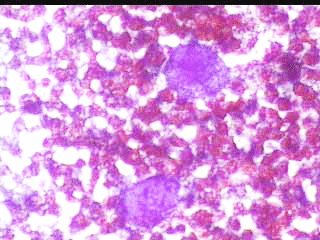

ΠPOEKEIMENOY NA ΔIAΠIΣTΩΘEI AN ΠPOKETAI ΓIA KYΣTH, ΠAPAKΈNTHΣH ΛEΠTHΣ BΛEONHΣ. ΠPOKETAI ΓIA ΣYMΠAΓH ΣXHMATIΣMO. ETΣΙ ΚΙ ΑΛΛΟΙΩΣ, ΠΡΕΠΕΙ Ν΄ ΑΦΑΙΡΕΘΕΊ.

Το ελάχιστο υλικό, επιστρώνεται σε αντικειμενοφόρο πλάκα, στεγνώνει στον αέρα και βάφεται κατά Papanicolaou . Δείγμα από τις κυτταρολογικές εικόνες